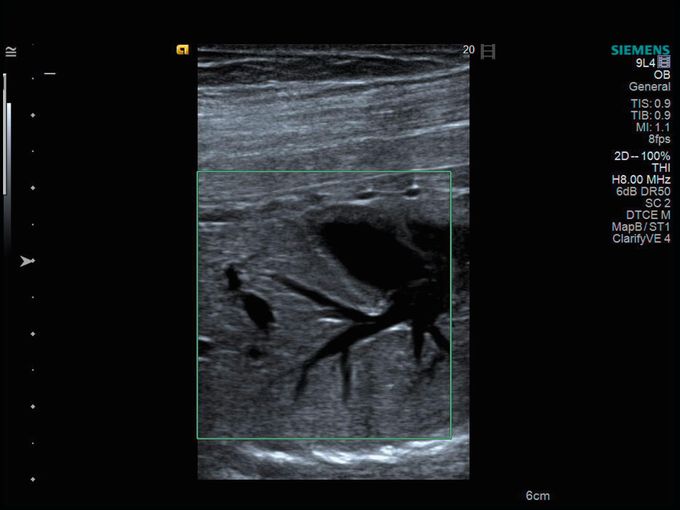

Кроме новой техники, можно заказать восстановленные медицинские системы: ультразвуковые сканеры, томографы, флюороскопы, ангиографы и хирургические установки С-дуга.